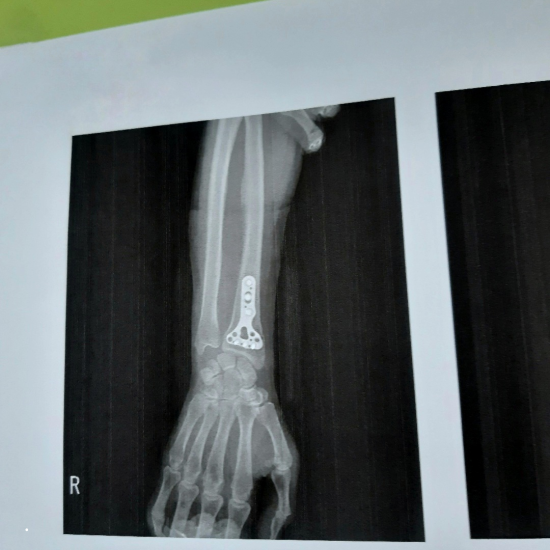

골절은 단순히 뼈가 부러지는 것을 넘어서 환자의 일상생활에 큰 지장을 주고, 때로는 치명적일 수도 있습니다. 특히 고관절, 손목, 척추 등 골다공증성 골절이 자주 발생하는 부위는 신중한 주의가 필요합니다.